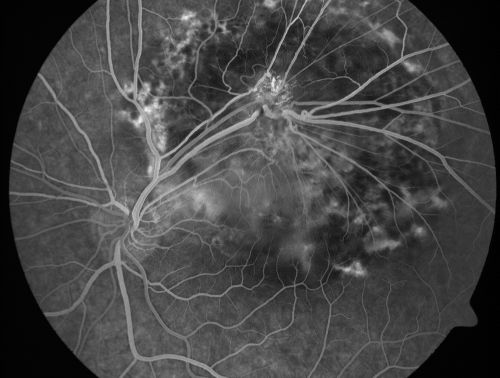

Retinal Pigment Epithelial Dysgenesis